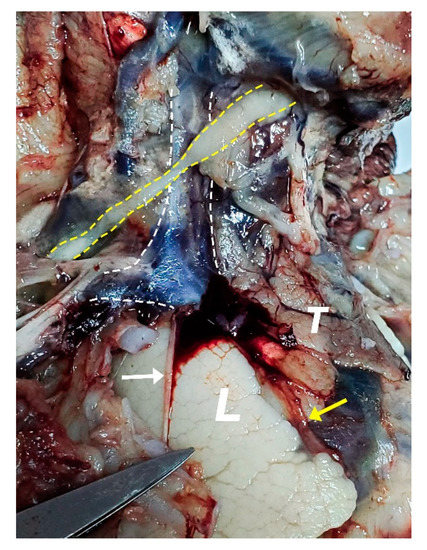

2.2. Dissection